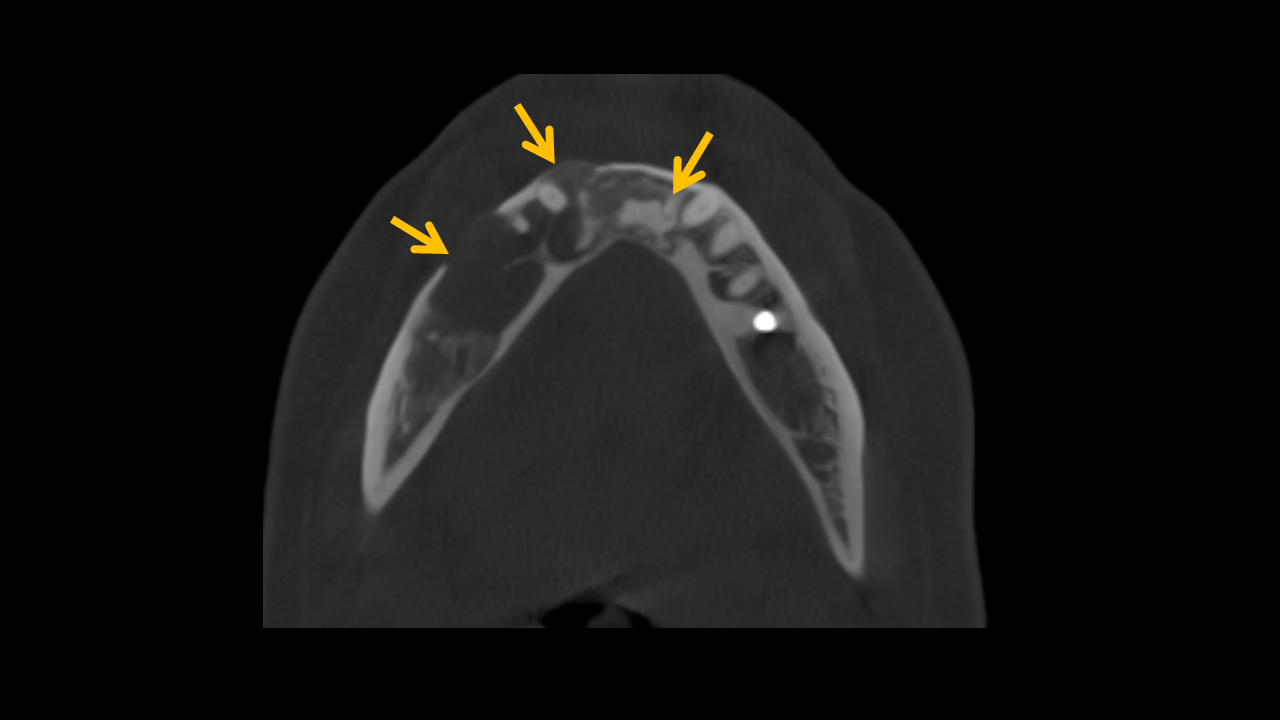

Study 3

Finding: There is an osteolytic lesion involving the right mandibular arch, characterized by effacement and expansion of the buccal and lingual cortices. Notably, there is destruction of the alveolar crest, and the cortical boundaries of the mandibular canal are eroded. These imaging findings are highly suggestive of a malignant lesion.